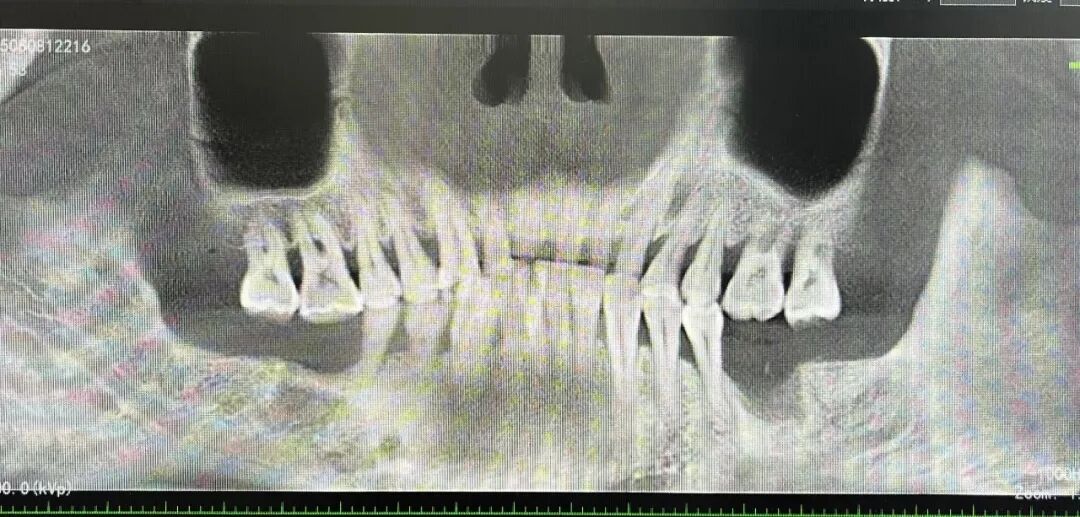

植牙焕新 重享口福

——种植牙技术成熟惠民生

十年磨一剑,科室种植牙技术历经多年打磨与实践,现已完全成熟开展,累计完成300例种植手术,成功实现隆阳人民拥有“第三副牙齿”的愿望。科室构建起从术前检查、方案设计,到种植手术、术后维护的全流程标准化诊疗体系,以精准的操作、规范的流程为缺牙患者提供安全高效的种植服务,有效解决老年患者缺牙咀嚼困难、中青年患者缺牙影响美观等问题,显著提升缺牙患者的生活质量。

种植前

种植后